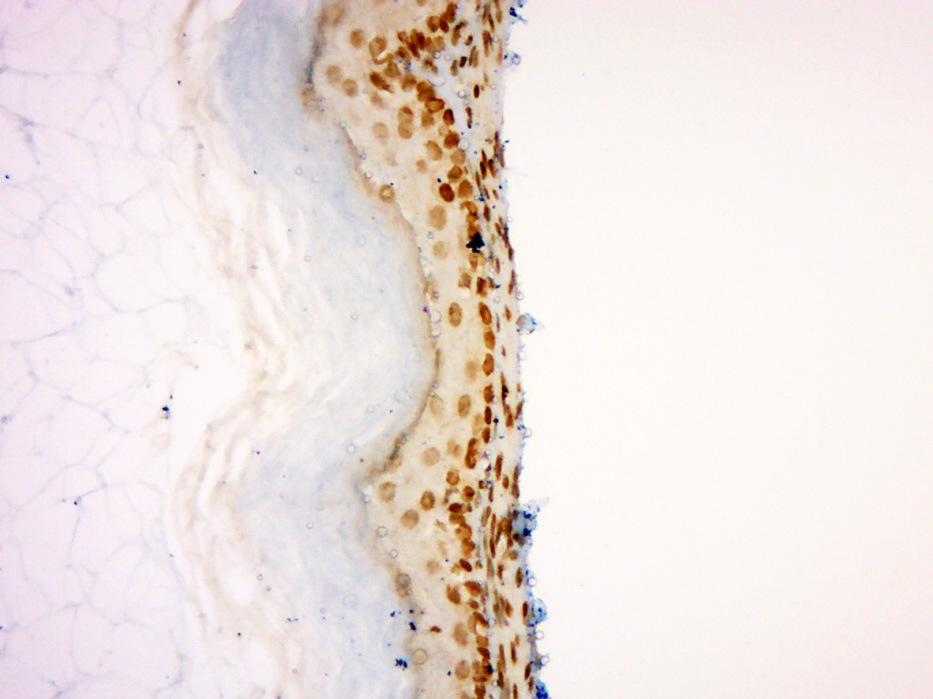

Paraformaldehyde-fixed, paraffin embedded (Mouse small intestine); Antigen retrieval by boiling in sodium citrate buffer (pH6.0) for 15min; Block endogenous peroxidase by 3% hydrogen peroxide for 20 minutes; Blocking buffer (normal goat serum) at 37°C for 30min; Antibody incubation with (Dnmt3b) Polyclonal Antibody, Unconjugated (bs-0301R) at 1:200 overnight at 4°C, followed by operating according to SP Kit(Rabbit) (sp-0023) instructionsand DAB staining.

Paraformaldehyde-fixed, paraffin embedded (Mouse stomach); Antigen retrieval by boiling in sodium citrate buffer (pH6.0) for 15min; Block endogenous peroxidase by 3% hydrogen peroxide for 20 minutes; Blocking buffer (normal goat serum) at 37°C for 30min; Antibody incubation with (Dnmt3b) Polyclonal Antibody, Unconjugated (bs-0301R) at 1:400 overnight at 4°C, followed by operating according to SP Kit(Rabbit) (sp-0023) instructions and DAB staining.